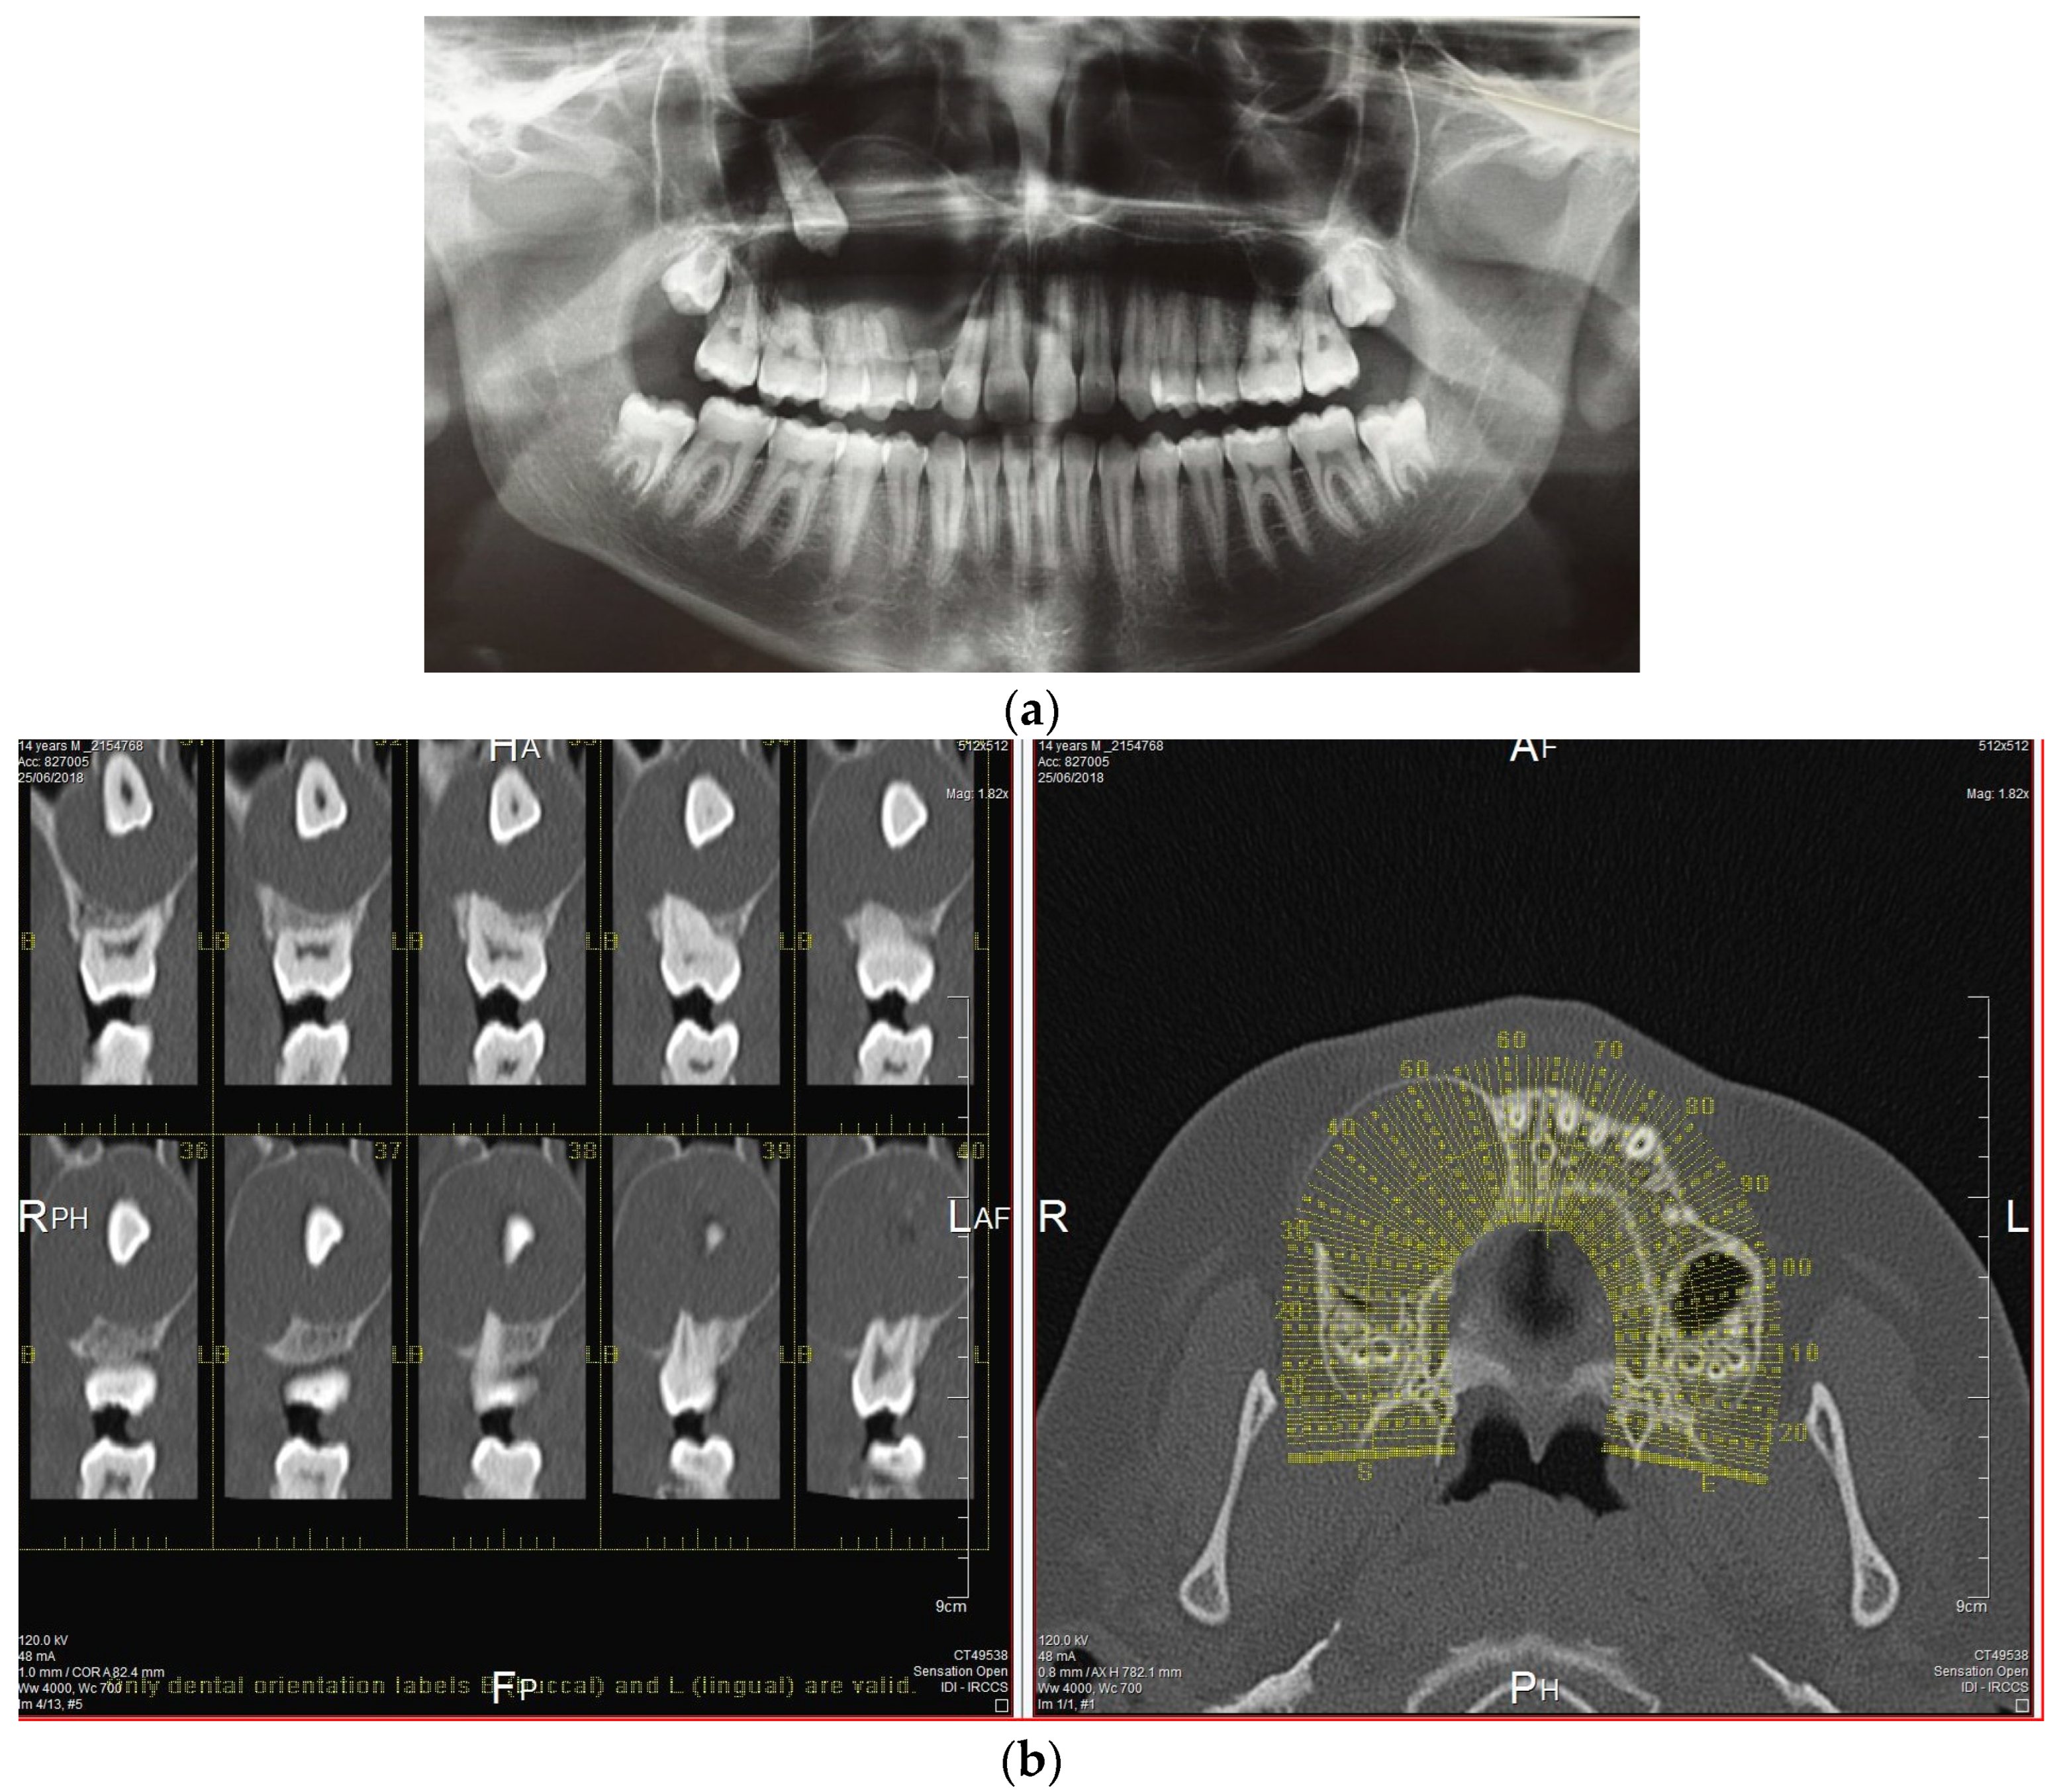

The treatment plan included the cystectomy and the surgical extraction of the impacted canine with the elevation of a full-thickness flap. The surgery was scheduled for local anesthesia. The complications of the surgery included communication with the maxillary sinus. Routine preoperative laboratory tests including a full blood count, blood clotting tests, azotemia, glycemia and creatinine levels were conducted. Additionally, a cardiologic evaluation, including an electrocardiogram, was performed. The patient was briefed on the potential risks and benefits associated with the surgical procedure. Informed consent was obtained, and the surgery was scheduled accordingly. After local anesthesia with three carpules of articaine hydrochloride + adrenaline 1:100,000, a full-thickness flap with a mesial release incision to the lateral incisor and distal to the first molar was performed by using a Bard–Parker #15 scalped blade. The flap was raised and held in place using a Langenbeck retractor (Figure 3), and the lesion was completely enucleated along with the impacted right maxillary canine (Figure 4). The permanent canine was entirely within the lesion. The tooth and lesion were removed together. Figure 5 shows the clinical aspect of the lesion. The lesion was entirely benign and encapsulated which allowed the roots of the involved dental elements (1.2, 5.3, 1.4, 1.5, 1.6) to be easily isolated during the enucleation. Saline solution rinses and closure with Vicryl 3.0 sutures were performed.

Figure 3. Detachment of the full thickness flap.

Figure 4. Complete enucleation of the lesion.